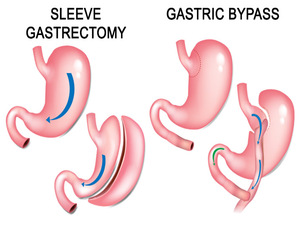

His special interests are in the field of Laparoscopic Hernia Surgery, Laparoscopic Upper G.I Surgery, Laparoscopy in Gastrointestinal Cancers and Bariatric Surgery. He is also actively involved in publications in peer – reviewed journals.